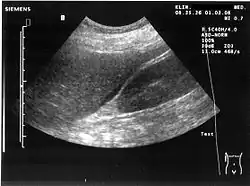

Zachyłek Morisona, zachyłek wątrobowo-nerkowy[1] – część jamy otrzewnej, przestrzeń oddzielająca wątrobę i prawą nerkę. W warunkach normy jest przestrzenią potencjalną, w której nie ma płynu; w razie krwotoku do jamy otrzewnej lub wodobrzusza gromadzi się w nim krew lub płyn przesiękowy, co można uwidocznić w badaniach obrazowych.